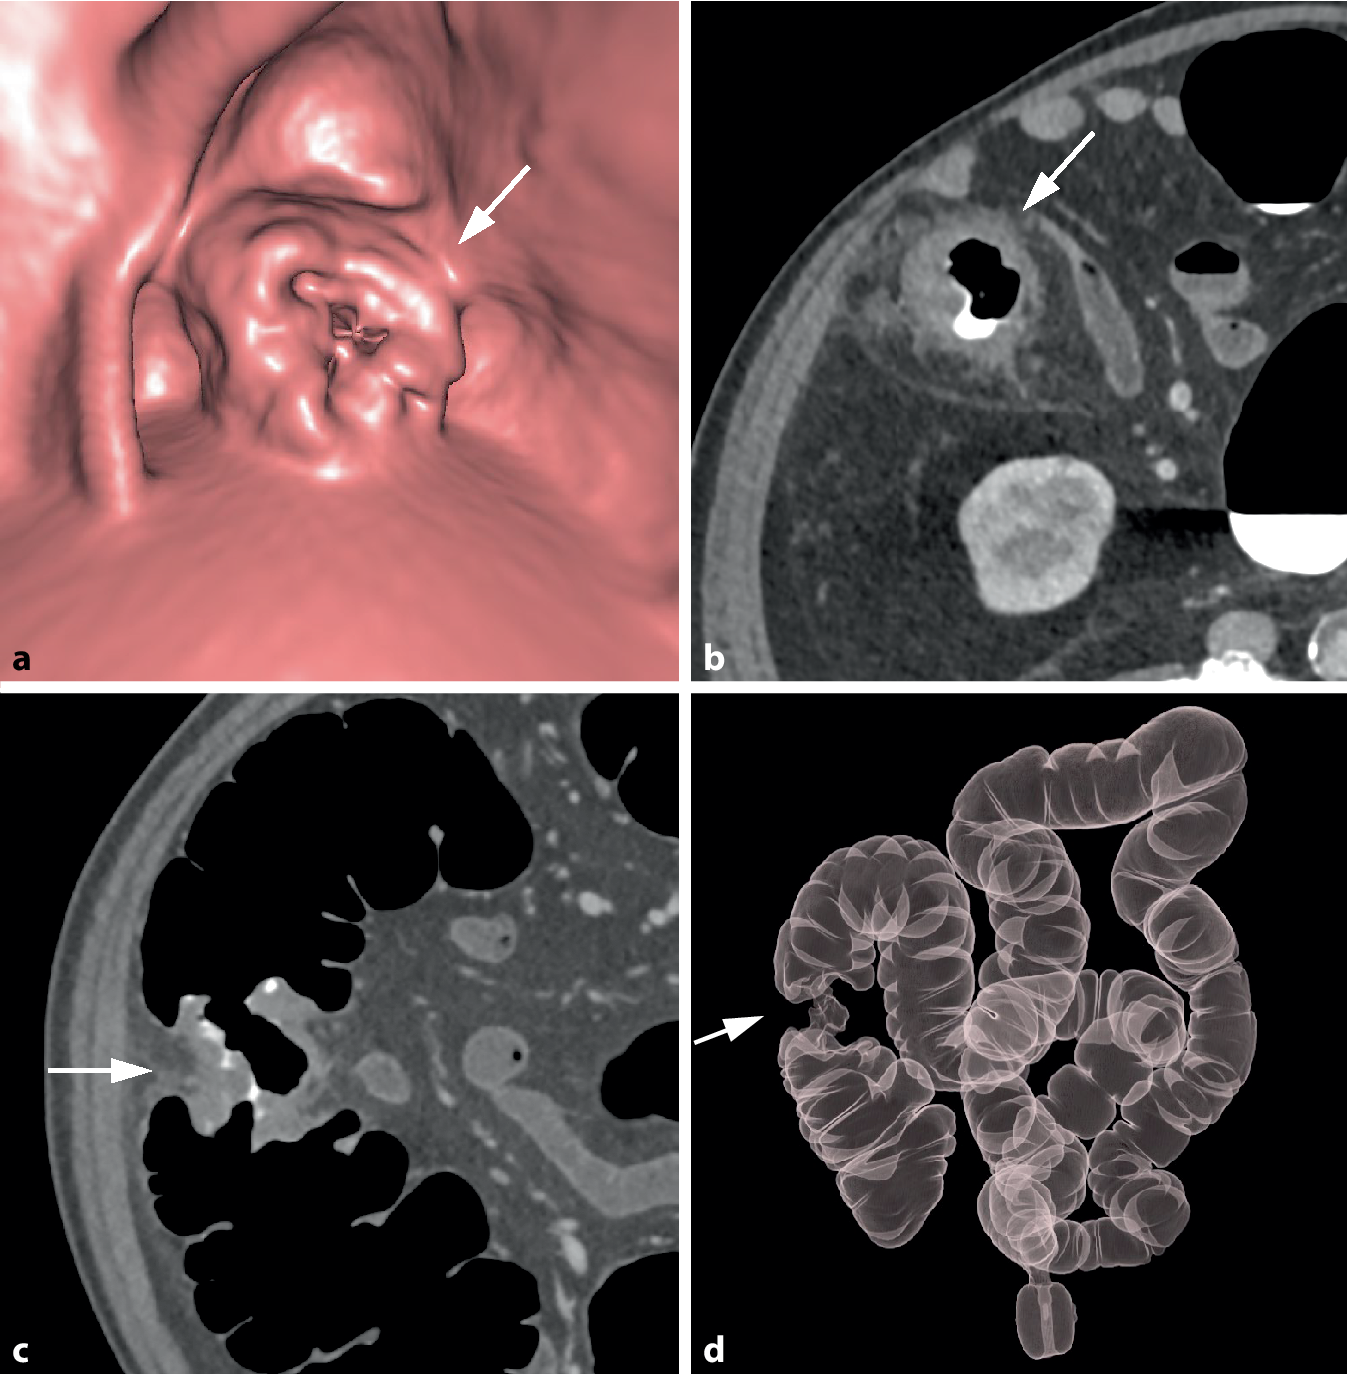

Bei zirkulär stenosierenden Tumoren umfasst die tumoröse Darmwandverbreiterung die gesamte Zirkumferenz des Darms (Abb. 2). Auf endoluminalen 3D-Ansichten erscheinen diese Karzinome meist als zirkuläre symmetrisch oder exzentrisch stenosierende Wandverbreiterungen. Das Ausmaß der Einengung des Darmlumens variiert und kann so ausgeprägt sein, dass diese Tumoren endoskopisch nicht passierbar sind.

Abb. 2

Zirkulär stenosierendes Karzinom im Colon ascendens bei inkompletter Koloskopie aufgrund einer Dickdarmelongation. a Die endoluminale 3D-Ansicht zeigt eine zirkulär stenosierende Raumforderung mit irregulärer Oberfläche und Schulterformation (Pfeil). b Das axiale 2D-Bild in Rückenlage zeigt die zirkuläre weichteildichte Wandverbreiterung (Pfeil). Es besteht eine unregelmäßige äußere Begrenzung mit nodulären Tumorinfiltrationen in das perikolische Fettgewebe sowie Fat Stranding als Zeichen der Wandüberschreitung (histologisch pT 3). c In der koronalen 2D-Ansicht ist die kurzstreckige weichteildichte tumoröse Wandverbreiterung mit Schulterformation (Pfeil) erkennbar. d In der globalen 3D-Ansicht zeigt sich die exakte Tumorlokalisation im Colon ascendens und der typische „Apple-core-Aspekt“ (Pfeil). Das Karzinom liegt bei 180 cm oberhalb des anorektalen Übergangs. Die Dickdarmgesamtlänge beträgt 220 cm

Bild vergrößern

Die longitudinale Ausdehnung der tumorösen Wandverdickung ist bei Karzinomen typischerweise kurzstreckig (< 5 cm) [12]. Der Übergang zur normalen Darmwand ist meist abrupt mit Ausbildung von überhängenden Tumorrändern, die auch als Schulterbildung bezeichnet wird. Bei zirkulär stenosierenden Karzinomen ergibt sich so besonders auf 3D-Übersichtsbildern das vom Kolonkontrasteinlauf bekannte Bild einer „apple core lesion“ (Abb. 2d).

Segmentale Tumorlokalisation

Die CTK liefert eine präzise Information über die segmentale Lokalisation von Tumoren im Kolon, die unverfälschte „In-vivo-Dickdarmgesamtlänge“, und die anatomisch-topografischen Gegebenheiten des Kolons (Abb. 2d). Derartige Informationen können für die Planung des chirurgischen Vorgehens hilfreich sein. Bei der Koloskopie wird hingegen der Dickdarm oftmals über das Endoskop geschoben, wodurch Längenangaben vom CTK-Befund deutlich abweichen können [18].